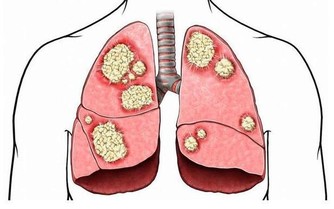

- 炎症與氧化壓力:某些情況下,過多的HDL可能失去其保護功能,反而引發炎症反應,加速動脈硬化進程。

- 與某些疾病的相關性:HDL過高可能與肝臟疾病、腎臟疾病或癌症風險增加有潛在關聯,但相關機制尚待進一步研究。